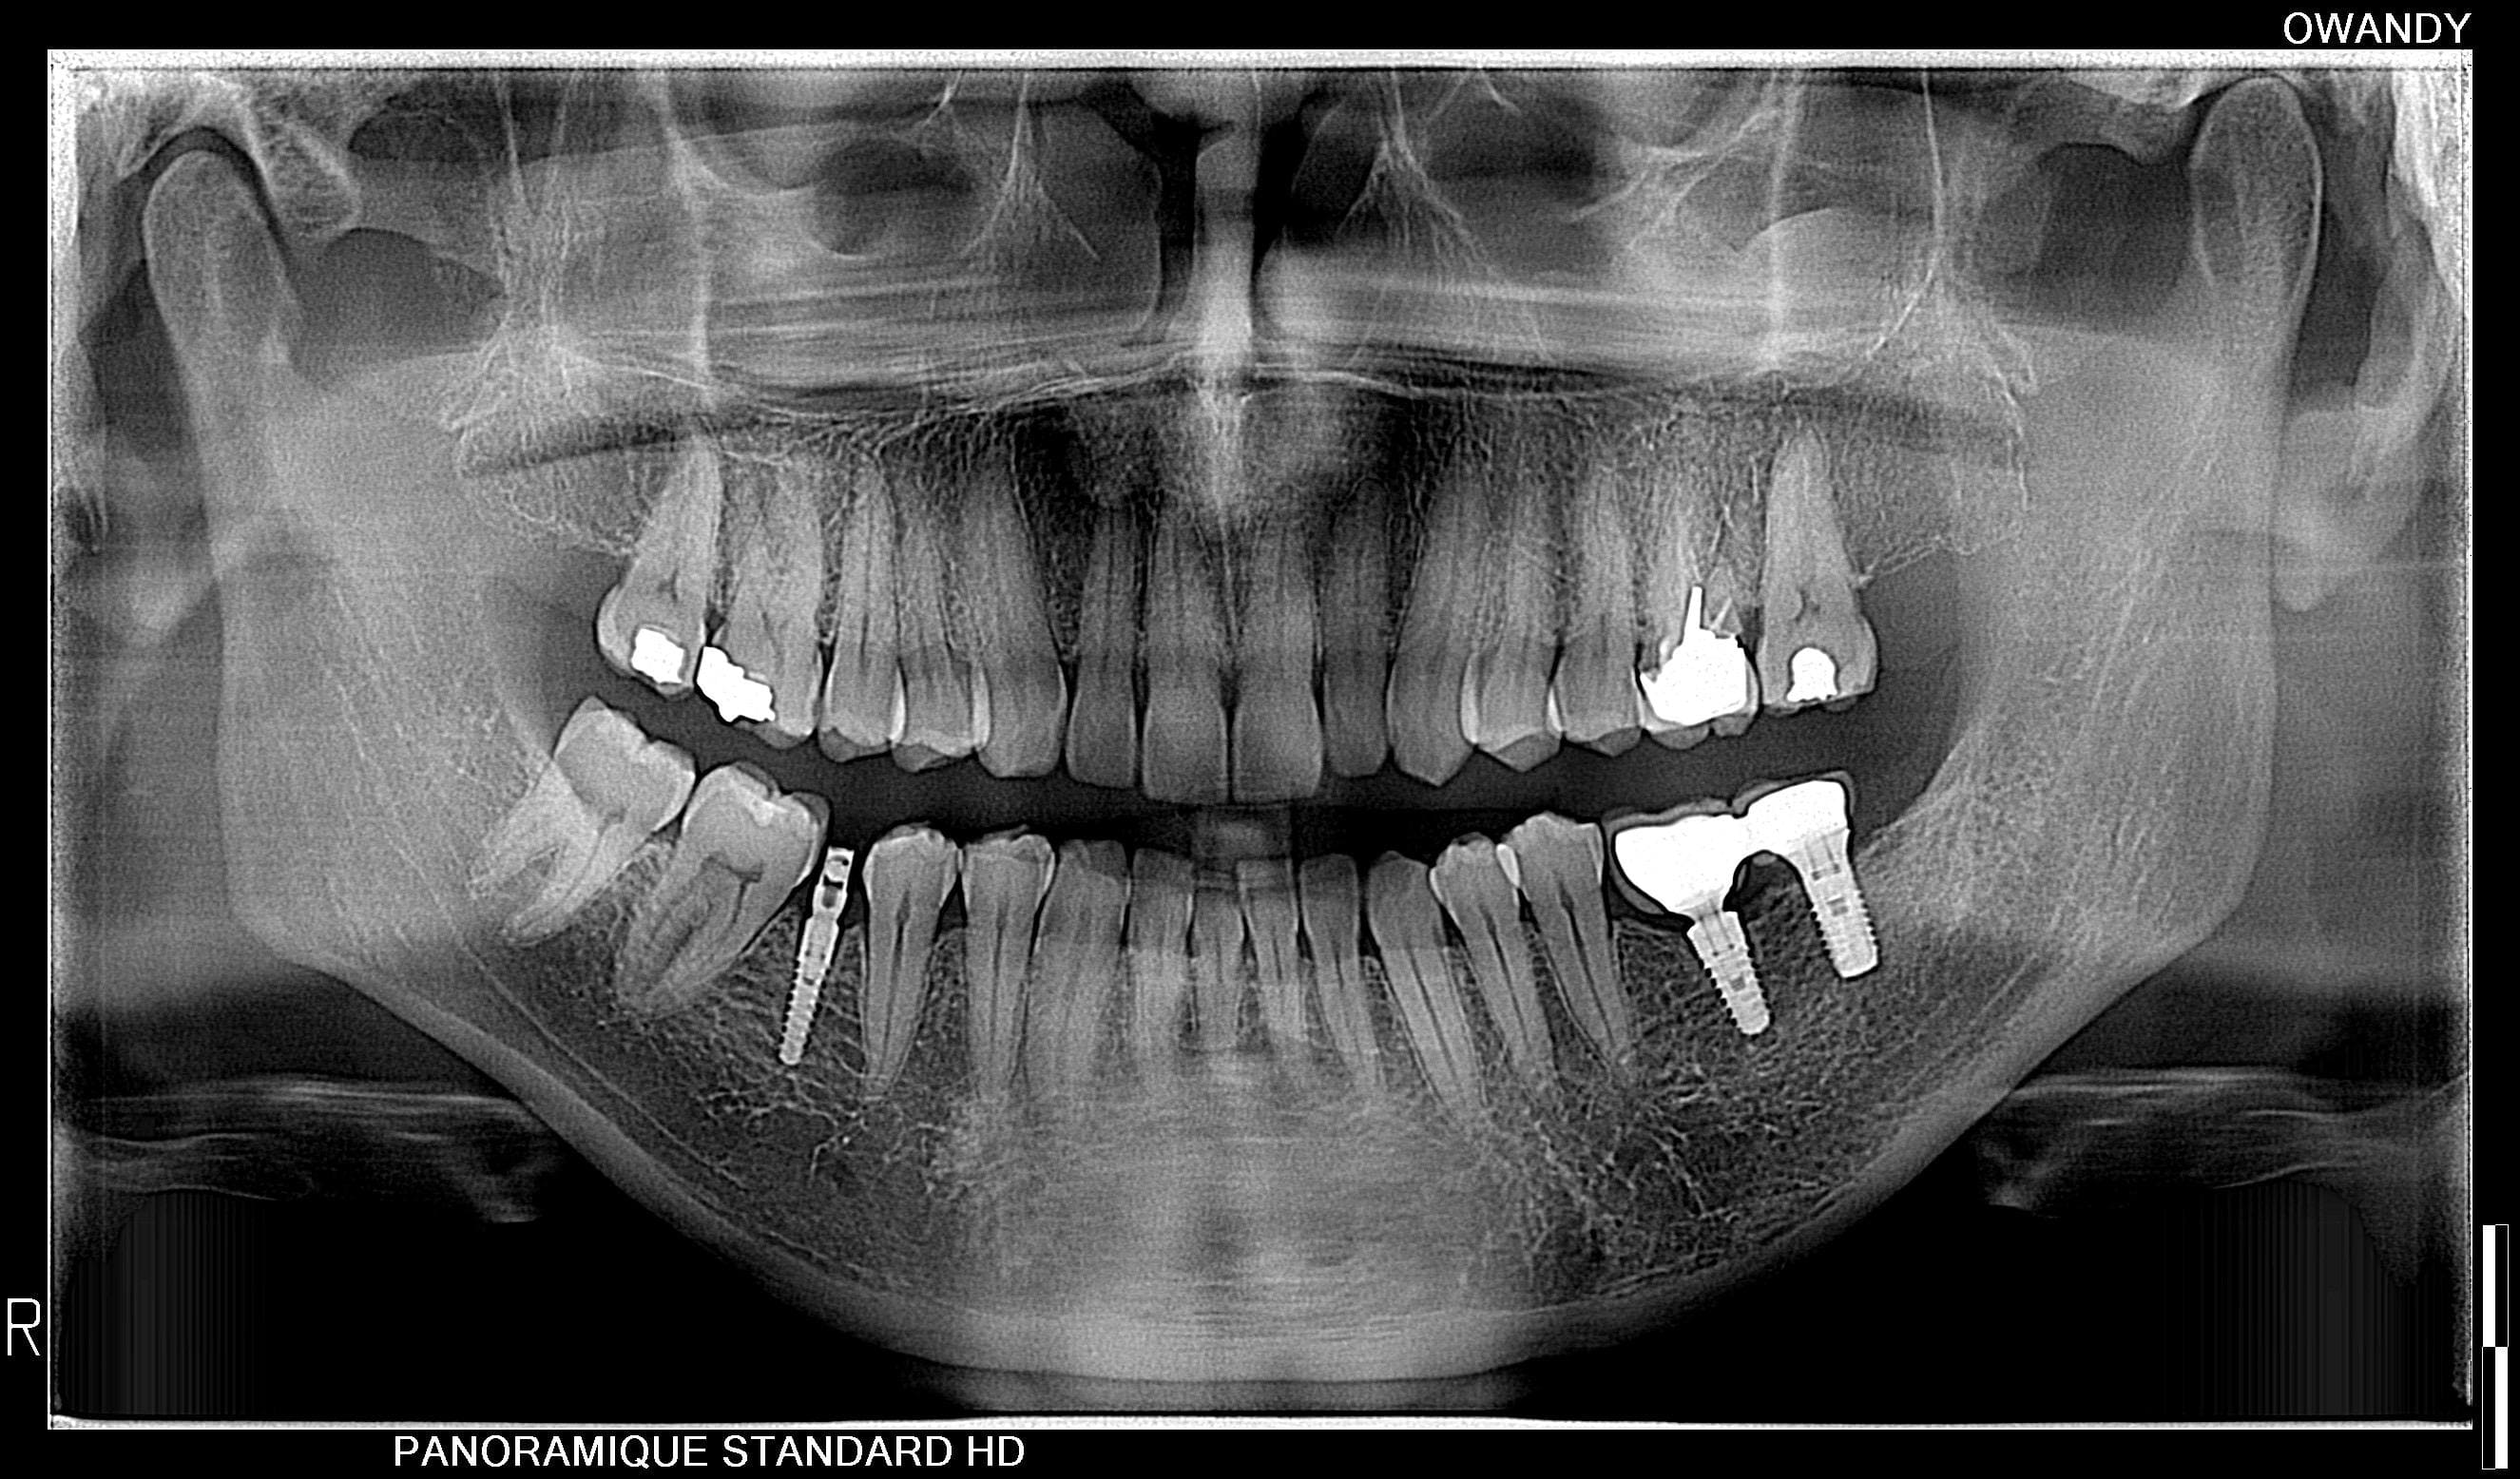

La radiografía panorámica es el examen 2-D de rutina más solicitado. Su potencial como herramienta diagnóstica radica en la posibilidad que tiene el odontólogo de observar la boca entera en una sola toma, incluyendo los dientes, la mandíbula, maxilar superior, y las estructuras y tejidos circundantes.

- De bajo costo

- rapidez

- mayor seguridad debido a la baja dosis y tiempo de exposición a la radiación.